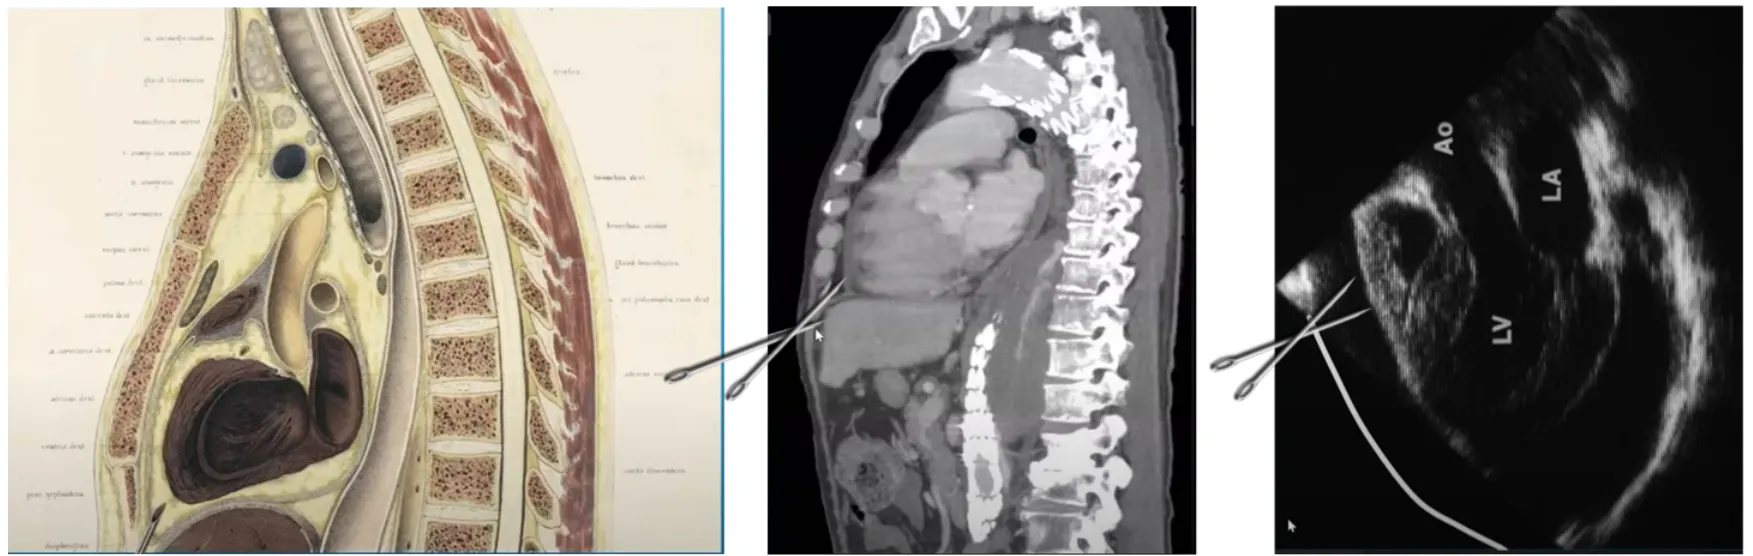

Subcostal technique

•

>익숙하고, 만약 응급상황에서 blind 로 해야된다면 가장 선호됨

단점으로는 liver 찌를 위험이 있고 찌르는 깊이가 깊음. 비만환자에서는 어렵

Subxiphoid 에서 insertion 하여 왼쪽 어깨쪽을 향해 넣음

Cartilage cage를 지나면 니들 앵글을 30도로 낮춘다

간 찌르지 않도록 조심

CT화면.초음파를 매칭해서 보면 알수있듯이 subcostal technique은 Liver 찌르기 쉬움

좀 더 superficial 한 각도, 적어도 45도~30도 각도로 넣어야 liver 찌르지 않고 pericardium 에 닿기 쉽다.